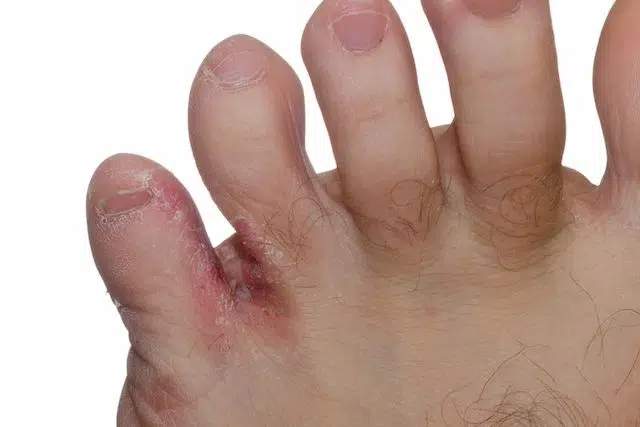

Pé de Atleta

O que é Pé de Atleta:

O pé de atleta, também conhecido como Tinea Pedis, é uma infecção fúngica que afeta a pele dos pés, especialmente entre os dedos e nas solas. Essa infecção é causada principalmente pelo fungo dermatófito, que prospera em ambientes quentes, úmidos e escuros, como os sapatos.

Sintomas:

Coceira intensa nos pés, especialmente entre os dedos.

Pele vermelha, escamosa ou descamativa.

Rachaduras ou fissuras na pele.

Sensação de queimação ou ardência.

Odor desagradável nos pés.